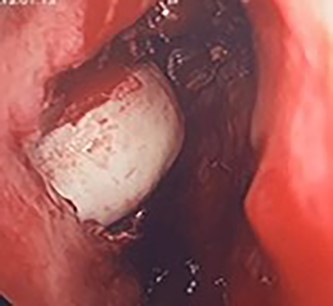

Flexible nasendoscopy offered little in terms of diagnostic benefit. An exam under anesthetic with a view to removing the ectopic tooth via endoscopic sinus surgery was warranted. Right middle turbinate trimming along with a right maxillary antrostomy was performed. The tooth was immediately identified at the antrum as depicted in Figs 4–6. The bony capsule of the tooth was entered and, on manipulation, a second ectopic tooth was identified (Fig. 7) both of which were removed en bloc. The cystic component within the maxillary sinus was marsupilized and extracted. The sinus cavity can be viewed with the utilization of 70° endoscope (Fig. 8). This facilitated bipolar cautery of the base of the cyst and confirmed the absence of an oroantral fistula.

Intra-operative image of the ectopic tooth at the right osteomeatal complex.